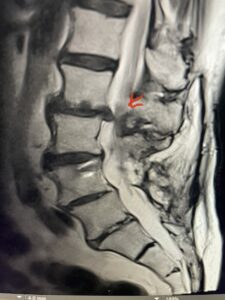

Fig 1a: Sagittal T2 weighted lumbar MRI demonstrating severe L2-3 stenosis (red arrow)

Fig 1b: axial T2-weighted MRI demonstrating severe lumbar stenosis (red arrow)